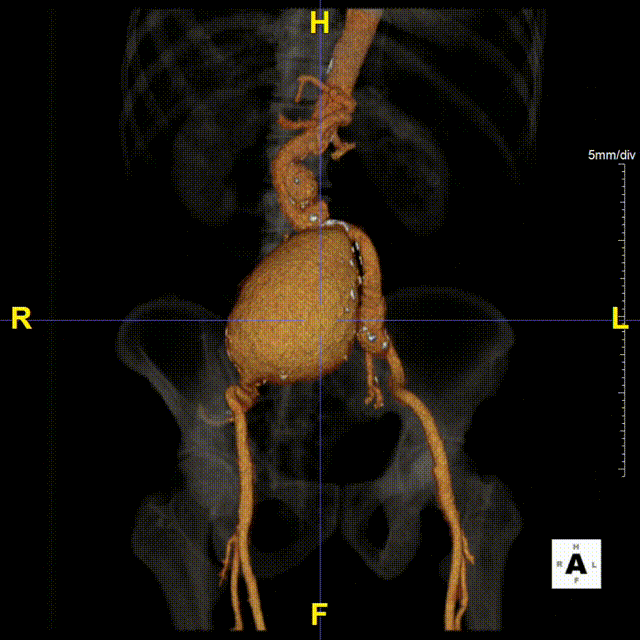

现病史:患者7小时前无明显诱因出现腹部胀痛不适,以下腹部为主,无发热、恶心、呕吐,无头晕、头痛等特殊不适,因症状持续不缓解,遂来我院急诊就诊,行腹主动脉(下腹部、盆腔段)CTA示:腹主动脉下段,右侧髂总动脉动脉瘤形成,右侧巨大髂总动脉(直径85.0mm*77.1mm)有明显造影剂溢出提示破裂,腹主动脉周围、左侧肾周、左侧腰大肌前缘及骶前积血较前明显增多,于急诊抢救室出现一过性意识丧失、血压下降休克状态,予积极补液后症状好转,现为进一步治疗,急诊以“腹主动夹层动脉瘤;髂动脉巨大动脉瘤破裂”收入院。

二、术前CTA详解

gore医疗怎么样「漫腹精论」髂合时宜 精益求精——双MOB球囊导管辅助腹主动脉覆膜支架急诊治疗破裂巨大髂动脉瘤_https://www.jmylbn.com_新闻资讯_第5张

gore医疗怎么样「漫腹精论」髂合时宜 精益求精——双MOB球囊导管辅助腹主动脉覆膜支架急诊治疗破裂巨大髂动脉瘤_https://www.jmylbn.com_新闻资讯_第6张

gore医疗怎么样「漫腹精论」髂合时宜 精益求精——双MOB球囊导管辅助腹主动脉覆膜支架急诊治疗破裂巨大髂动脉瘤_https://www.jmylbn.com_新闻资讯_第7张

gore医疗怎么样「漫腹精论」髂合时宜 精益求精——双MOB球囊导管辅助腹主动脉覆膜支架急诊治疗破裂巨大髂动脉瘤_https://www.jmylbn.com_新闻资讯_第8张

gore医疗怎么样「漫腹精论」髂合时宜 精益求精——双MOB球囊导管辅助腹主动脉覆膜支架急诊治疗破裂巨大髂动脉瘤_https://www.jmylbn.com_新闻资讯_第9张

gore医疗怎么样「漫腹精论」髂合时宜 精益求精——双MOB球囊导管辅助腹主动脉覆膜支架急诊治疗破裂巨大髂动脉瘤_https://www.jmylbn.com_新闻资讯_第10张

gore医疗怎么样「漫腹精论」髂合时宜 精益求精——双MOB球囊导管辅助腹主动脉覆膜支架急诊治疗破裂巨大髂动脉瘤_https://www.jmylbn.com_新闻资讯_第11张